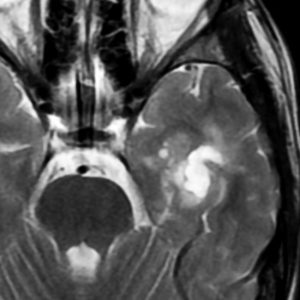

もともと停止性水頭症があり経過観察を受けていたNF-1の患者さんに発生したものです。嘔気と左片麻痺で発症しました。 開頭手術で亜全摘出(ほぼ全摘)しました。

術後に小さな腫瘍が残っていた(左の画像)ので54Gy/27frの放射線治療をしましたが,無効でした。結局,再開頭手術で残存腫瘍を摘出しました。3年後に同じ部位で再発(中央の画像)したので,また開頭手術で摘出しました。そのまた3年後に同じ部位で再発しました(右側の画像)。この様に,摘出しきれなければ治らないし,摘出できれば治る可能性の高い腫瘍です。腫瘍床での再発は多いものの,転移とか脳深部への浸潤性増殖は少ないといえる腫瘍です。放射線治療が効きにくいということを併せて,atypical meningioma WHO grade 2と似た性格を有しています。